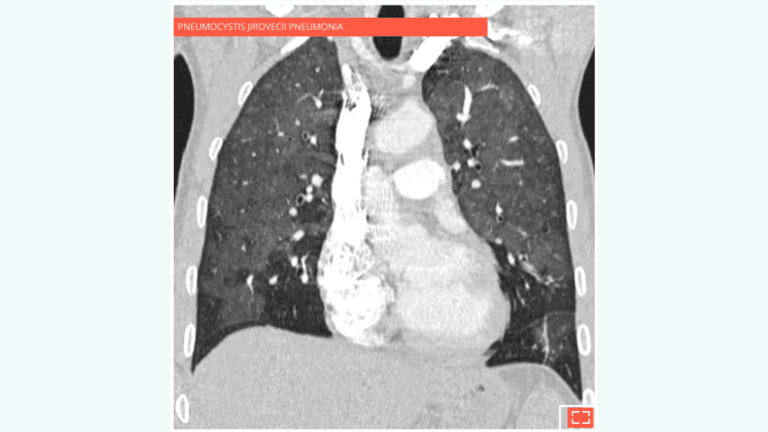

• Pulmonary infection: pneumocystis jirovecii pneumonia, cytomegalovirus (CMV), etc.

Diffuse ground-glass opacity of the lung sparing subpleural areas.